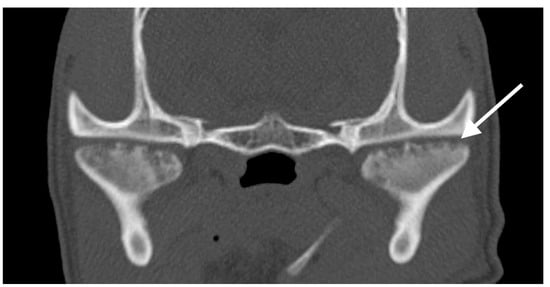

A CT examination of the neck, thorax, and abdomen was performed before and after intravenous administration of iodinated non-ionic contrast medium. The scan field of view included the proximal forelimbs to the mid-diaphysis of the radius and ulna, as well as the proximal hindlimbs to the distal femurs. CT findings showed bilateral symmetric changes in the proximal humeral metaphysis, consisting of an ill-defined, irregular hypoattenuating band of moth-eaten to permeative lysis parallel to the physis (Figure 3). Adjacent areas of metaphyseal sclerosis were observed, along with mild smooth periosteal new bone formation at the caudoproximal humeral metaphysis and proximal diaphysis bilaterally. The physes appeared normal. Mild generalised superficial lymphadenomegaly was present, which was considered to be a normal age-related finding or mild reactive hyperplasia. The CT findings were suggestive of MO.

Due to the potential need for follow-up imaging, orthogonal radiographs of both distal forelimbs, both stifles, and a mediolateral view of the right shoulder were obtained (Figure 3B). An irregular, radiolucent metaphyseal band parallel to the physis was observed within the proximal right humerus, bilateral distal femur, radius and ulna, and bilateral proximal tibia. Moderate sclerosis of the adjacent metaphyseal bone was present, along with a faint, solid periosteal reaction at the caudal aspect of the proximal right humeral metaphysis. The radiographic findings supported the presumed diagnosis of MO.

Figure 3. Case 2. Sagittal Multiplanar Reconstruction (MPR) image with bone algorithm of the proximal humerus on CT (A) and mediolateral radiographic view of the proximal humerus (B). In both images, an ill-defined, irregular lucent band of lysis is present within the proximal humeral metaphysis parallel to the physis (white arrows) with mild associated bone sclerosis.